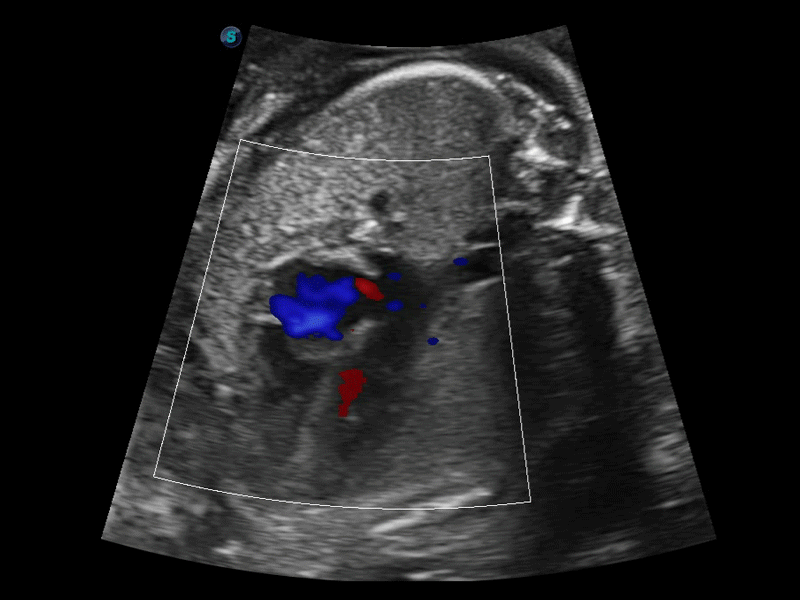

S-Fetus 产科扫查助手

S-Fetus基于大数据深度学习算法,能够帮助您在产前筛查过程中智能识别胎儿标准切面、自动测量并录入报告。一个按键,即可智能、精准、高效地获取胎儿生理指标,极大简化您的产科检查操作。

临床图像